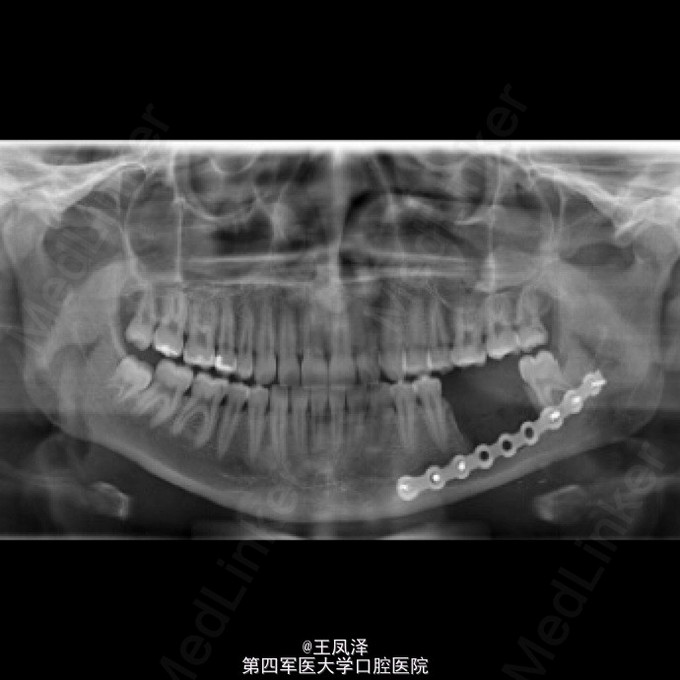

罕见左侧下颌骨牙本质生成性影细胞瘤一例

患者,女,20岁,自诉左侧下颌磨牙区疼痛不适,不能咀嚼来诊

以巨大囊肿为表现的牙本质生成性影细胞瘤